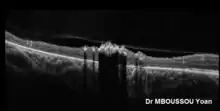

Coupe OCT d'une atrophie choriorétinienne paraveineuse pigmentée